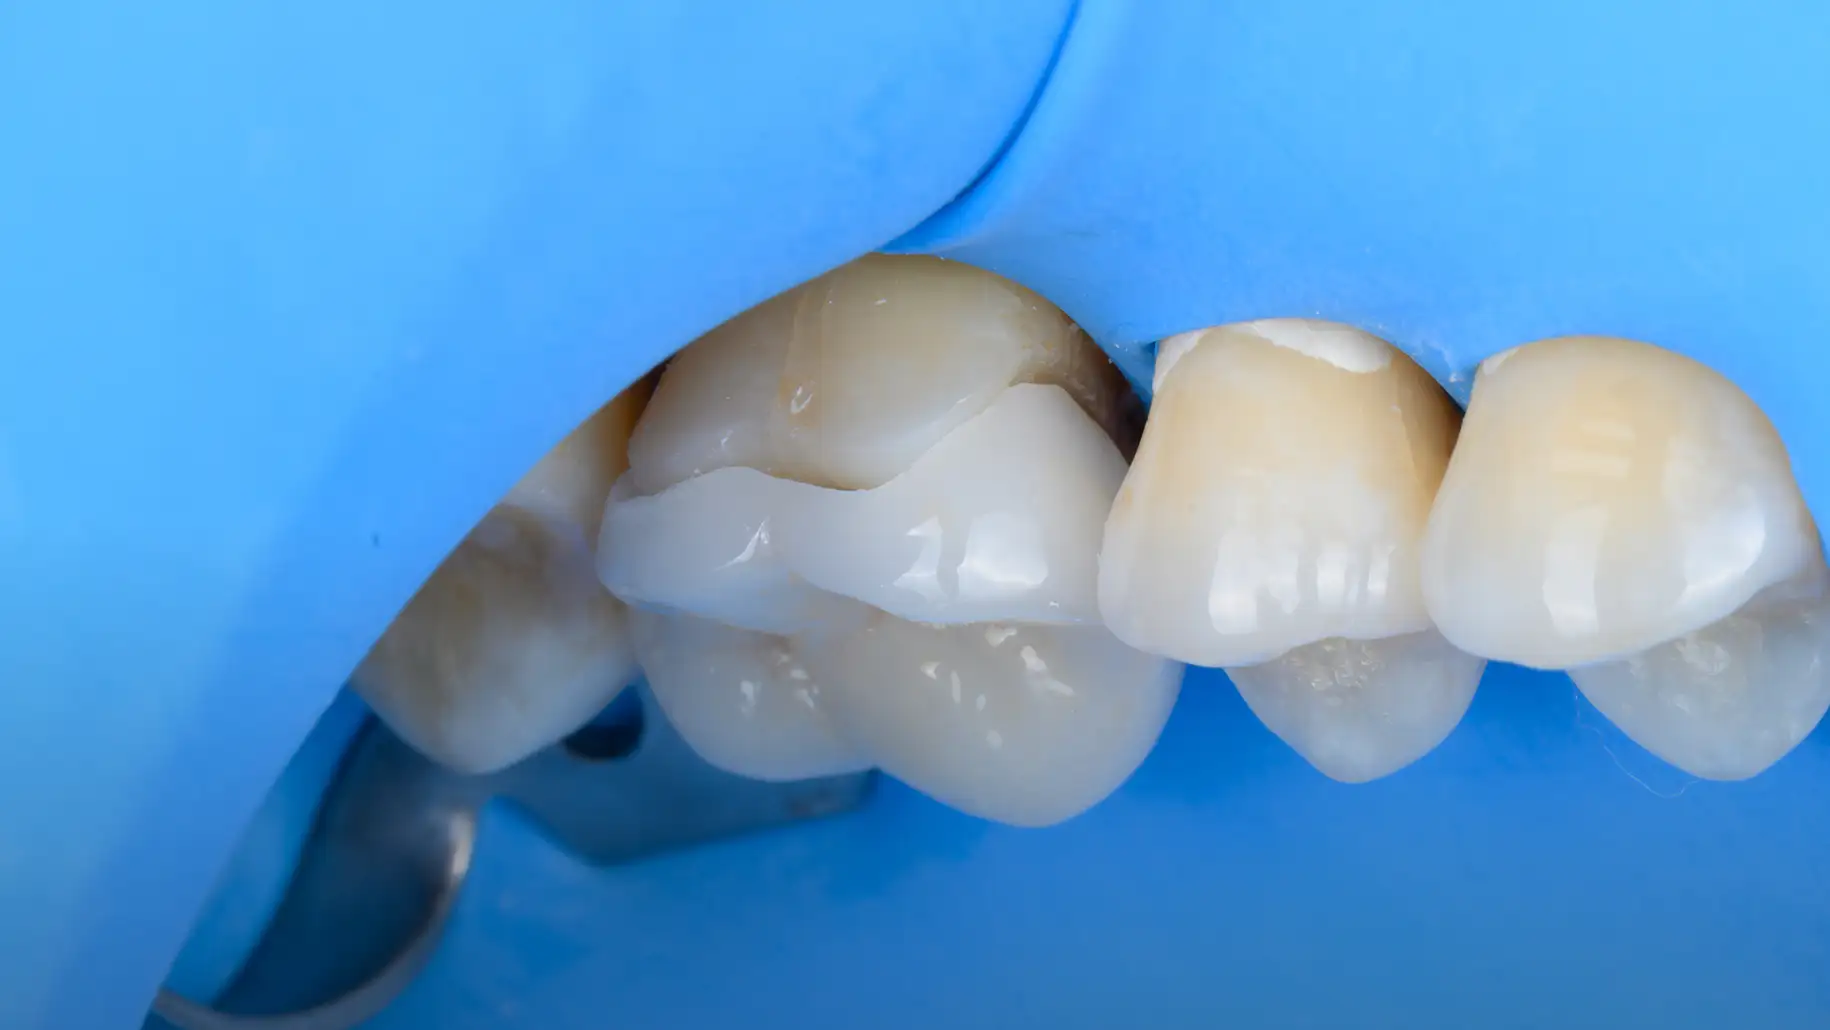

본 사례들은 동일한 조건하에 촬영된 실제 임상 사진이며, 환자분의 동의를 얻어 게재되었습니다. 의료법 제56조 제1항에 따라, 치료 결과는 환자분의 구강 환경, 식습관 및 사후 관리 정도에 따라 차이가 있을 수 있습니다. 레진 수복 치료 후 일시적인 시린 증상이 나타날 수 있으며, 시간이 흐름에 따라 수복물의 변색이나 마모, 탈락이 발생할 수 있으므로 정기적인 검진을 권장합니다.

해부학적 형태의 정밀 복원

간접 수복은 구강 외에서 수작업으로 보철물을 제작합니다. 정교하게 치아의 해부학적인 형태를 복원하고, 교합 관계를 회복시킵니다.